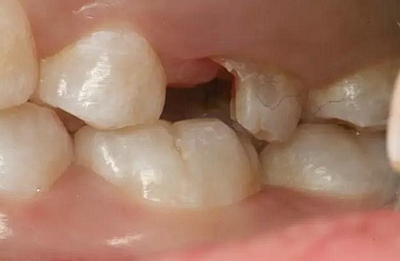

患者男性,35歲,B6銀汞充填后食物嵌塞,要求重新充填,口內(nèi)檢查見B6近中鄰頜面銀汞充填物,局部缺損,有繼發(fā)齲,去除原充填物及繼發(fā)齲,發(fā)現(xiàn)齲壞位于牙齦下方,給予冠延長手術,同期嵌體預備,后一次性取模。(同樣設計為齦上邊緣)

硅橡膠取模后,灌注模型,科爾琥珀樹脂制作嵌體。

一周后拆線,口內(nèi)試戴合適,粘結嵌體。